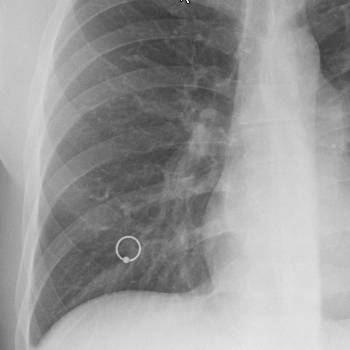

폐렴은 다양한 원인에 의해 발생하는 폐의 염증 질환으로, 여러 가지 증상을 동반할 수 있습니다. 폐렴의 증상은 감염의 원인, 환자의 연령, 건강 상태 등에 따라 다를 수 있지만, 일반적으로 나타나는 주요 증상은 다음과 같습니다. 전문가적 입장에서 폐렴의 증상 10가지를 상세히 설명하겠습니다.

폐렴은 다양한 증상을 동반하는 심각한 질환으로, 증상이 나타날 경우 즉시 의료 전문가의 도움을 받아야 합니다. 폐렴의 증상은 감염의 원인, 환자의 나이와 건강 상태에 따라 다르게 나타날 수 있지만, 앞서 언급한 10가지 증상은 일반적으로 관찰되는 주요 증상입니다. 폐렴의 조기 진단과 적절한 치료는 합병증을 예방하고, 회복을 촉진하는 데 매우 중요합니다. 따라서, 폐렴의 증상이 나타나면 지체 없이 의료 기관을 방문하여 적절한 진단과 치료를 받는 것이 중요합니다.